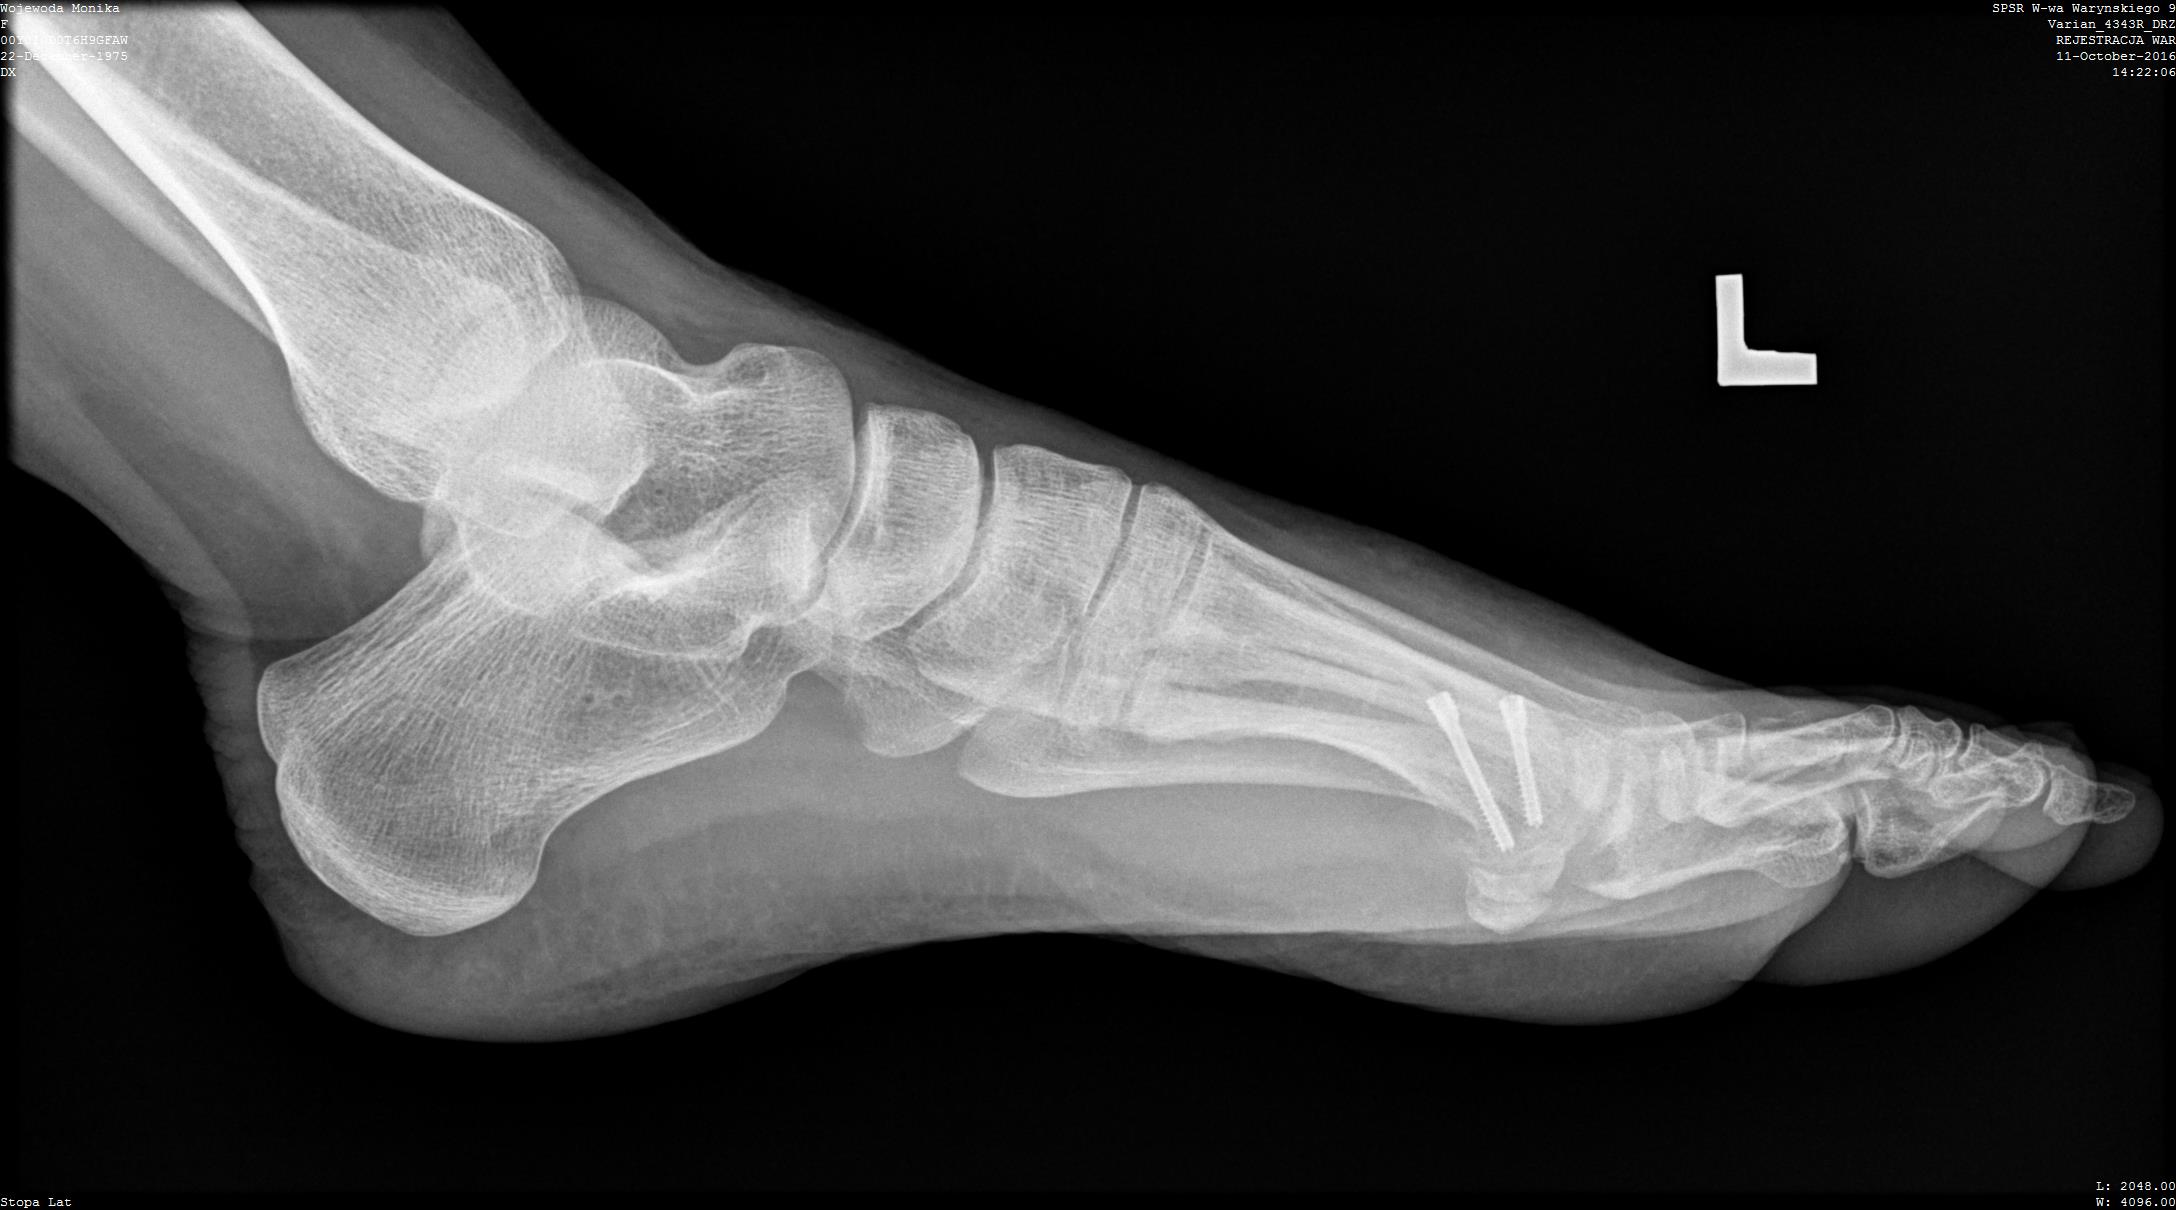

- artrodeza (usztywnienie) stawu MTP I – polega na usunięciu ze stawu resztek chrząstki stawowej. Następnie za pomocą płytki i wkrętów łączymy paluch i I kość śródstopia. Dochodzi do zrostu kostnego w obrębie wcześniej występującego stawu. Staw jest od tego momentu sztywny, ale niebolesny. Wbrew pozorom, chodzi się całkowicie normalnie. Większość pacjentów jest również w stanie uprawiać sporty.